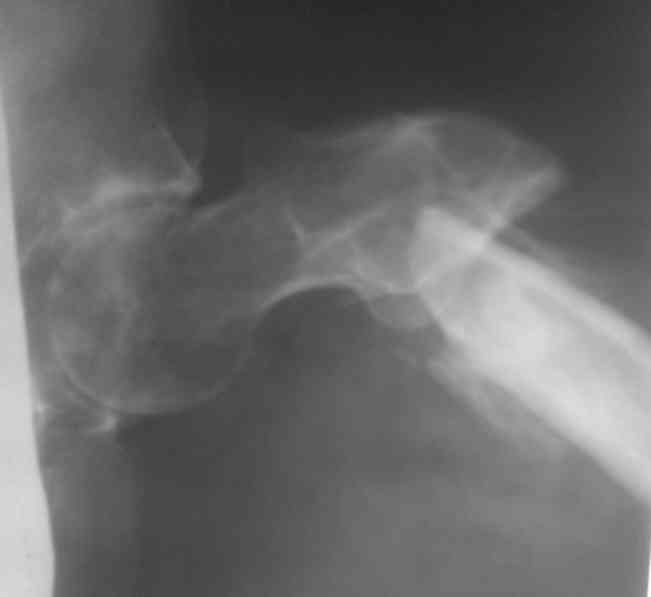

Больной 48 лет, 1,5 года с момента травмы!!Лечился в местной больнице скелетным вытяжением в течение 2 месяцев!!Поступил для оперативного лечения. Выраженное укорочение конечности на 10 см., с наружной ротацией,С патологической подвижностью. Уважаемые коллеги - что вы предложите для Коррекции перелома и устранения ложного сустава, и какие виды операций для устранения укорочения!!Какой метод фиксации? С уважением!!!!

А при чем тут шейка бедра? На снимке подвертельный ложный сустав. И вторую проекцию бы посмотреть.

У нас бы аппаратом устранили укорочение, исправили ось, лучше с гипервальгизацией, да и закрыто заштифтовали бы. Подойдет реконструкционный, проксимальный или гамма, и даже некоторые диафизарные, с бОльшим числом статических винтов. Можно и другие фиксаторы - и клинковая пластина, и DHS/DCS... Наверно, много где и аппаратом до сращения бы фиксировали.

Название темы- это произвольно!! Второй снимок прилагаю!!!

по поводу соображения!!! Будем идти в два этапа:вероятно будем растягивать ложняк на столе Хоули с учётом ротаций, идти открыто,фиксировать пластиной в шейку- добится консолидации, а затем удлиним в аппарате!!Или сразу Аппарат????

По-моему, этот план самый трудоемкий и травматичный. Если наложить сейчас аппарат закрыто, все за 2-3 недели исправить в аппарате, а вторым этапом зафиксировать отломки пластиной, с пластикой или без - решить по снимкам перед этим. Пластинку при восстановленной заранее анатомии делать будет нетрудно, не надо будет скелетировать и мобилизовать отломки.